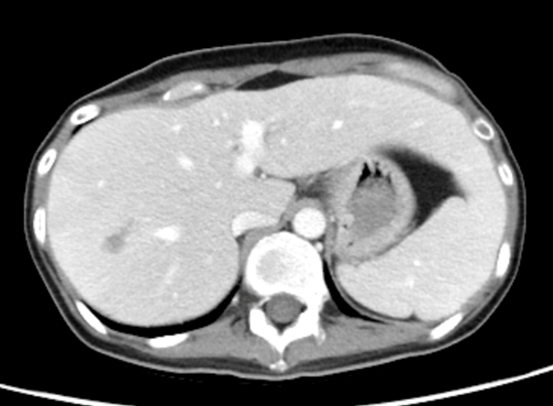

Peripheral blood mononuclear cell EBV PCR elevating from 23,709 to 68,100 IU/ug of genomic DNA occurred 6 months after first transplant. The patient initially responded to four weekly doses of rituximab 375 mg/m2, but elevated EBV PCR recurred in 2 weeks after rituximab was discontinued. There was still response after rituximab was resumed; however, there was no more response to the subsequent rituximab treatment 2 months later, and both plasma and PBMN cell EBV PCR elevated to 235,767 IU/ml and 218,411 IU/ug of genomic DNA, respectively, before second haplo-transplant. At the same time, we found there were scattered intrahepatic nodules, which proved to be EBV-related PTLD after liver biopsy performed.

Plasma and peripheral blood mononuclear cell EBV were dropped dramatically from 235,767 IU/ml and 218,411 IU/ug on day -1 to 1,177 IU/ml and 1,747 IU/ug, respectively, on day +6 and then declined gradually until they were undetected on day +34 (figure 1). Prior “intrahepatic PTLD nodules” biopsy performed on +20 days showed total necrotic tissues except one cell stained positive for EBV, indicating the prior intrahepatic PTLD became necrotic and resolved in the subsequent months (Figure 2). At the time of report in July 2022, the patient got well and is living with persisted PTLD-free conditions in liver and undetected EBV PCR in plasma and PBMN cell as well.

Figure 2A Intrahepatic infiltrative lesions 4 weeks before second haplo-transplant.

2020/12/28